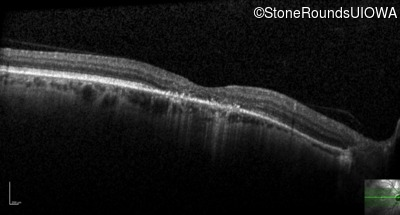

This 52 year old man had normal vision until his mid 30's when he began to have trouble distinguishing colors. the issuing 10 years he had a gradual loss of visual acuity accompanied by increasing photophobia.

| Age at visit: 61 years |